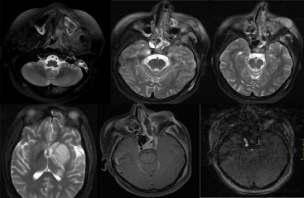

Emphysematouspyelonephritis–inanon-diabeticyoungwomen

—arareassociation— Y S Ravikumar, K M Srinath, L S Adarsh, Manjunath S Shetty, Subrahmanyam Karuturi, B Balaji Kirushnan .................................................108 Rhinocerebralmucormycosis:reportoftwocasesandreviewofliterature — Gopee E Makwana, Vikash Jain, Nandini Bahri, Mala Sinha, Manish Kumar Mathur.................110 Harlequinichthyosis—acasereport— Sendhil Coumary A, Seethesh Ghose .................................113 ..............................................................................................................................................116